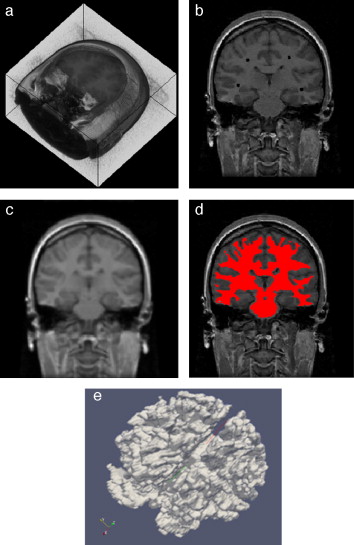

3.4. Modelado del hueso cráneo-facial

En imágenes de TC, las estructuras óseas son representadas con niveles de gris más altos comparado con los otros tipos de tejidos presentes en estas imágenes, debido a esta característica resulta útil aplicar técnicas de umbralización para separar este tipo de tejidos óseos de los demás. Sin embargo, el uso de umbralización puede tener la desventaja de generar pequeñas zonas desconectadas dentro de la misma estructura o fuera de ésta y a la vez generar zonas superpuestas en las superficies de los huesos, por los cuales se hace necesario aplicar técnicas de filtrado y suavizado de ruido antes de segmentar, así como realizar un remuestreo de los modelos segmentados aplicando técnicas de dilatación morfológica para rellenar los agujeros presentes y suavizar capas externas de los modelos óseos.

Para verificar la correcta combinación de estas técnicas y su utilidad, éstas fueron aplicadas en imágenes de TC del cerebro para obtener el modelo geométrico del hueso cráneo-facial, el flujograma de algoritmos utilizado es presentado en la figura 21 . Cada proceso es descrito a continuación.

Figura 21. Flujograma para la obtención del modelo del hueso craneal. |

3.4.1. Preproceso

Para la reducción del ruido de las imágenes de TC se aplicó el filtro de difusión anisotrópica, asimismo, se consiguió uniformizar los niveles de gris de los tejidos en la imagen.

3.4.2. Segmentación

Para segmentar el hueso del cráneo se utilizó la técnica de umbralización. Se observó el histograma global de la imagen y se seleccionó un valor umbral que separara el tejido óseo de los demás tejidos, obteniéndose una imagen binaria. Orientados por la escala de Hounsfield[1], en imágenes de TC correctamente calibradas, los valores del hueso compacto son superiores a 1.000.

3.4.3. Remuestreo y exportación a CAD

Para suavizar las superficies y rellenar los agujeros generados por la técnica de segmentación empleada se aplicó dilatación morfológica con un elemento estructural esférico de radio 3 × 3 × 3 . Este modelo fue guardado en formatos legibles por software de visualización y herramientas CAD como GiD, ParaView, Autodesk Inventor y Abaqus.

En la figura 22 se presenta la segmentación del cráneo en imágenes de TC en formato DICOM, 256 slices , tamaño de corte de 512 × 512 pixels, voxel spacing: 0,98 × 0,98 × 1,0 mm. Para obtener un valor umbral que distinga el tejido óseo de los demás tejidos, se analizó el histograma global de la imagen, donde claramente se observa que el tejido óseo posee los niveles de gris más altos. En este caso de estudio en espacial, los voxels de la imagen de entrada menores a un umbral de valor 1.266 fueron convertidos a negro, y los voxels con valores mayores al umbral fueron convertidos a blanco. De este modo, se obtuvo un volumen binario del hueso craneal.

Figura 22. Técnica de umbralización aplicada a TC. (a) Vista original de un corte axial de TC. (b) Imagen filtrada con difusión anisotrópica. (c) Histograma de imagen b. (d) Imagen binaria resultante de umbralizar imagen b con un umbral de 1266. |

El modelo geométrico del cráneo obtenido con la metodología es presentado en la figura 23 . Las vistas presentadas en la figura han sido generadas empleando ParaView.

Figura 23. Vistas volumétrica del modelo del cráneo. (a) Vista del volumen original en ParaView. (b) Vista de la superficie del cráneo en GiD. |